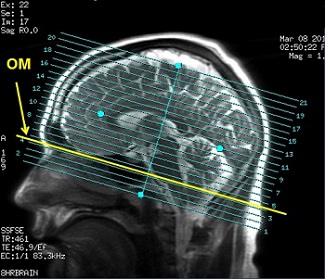

OM set the Orbitomeatal line, which extends from the nasal root through the pontomedullary junction.